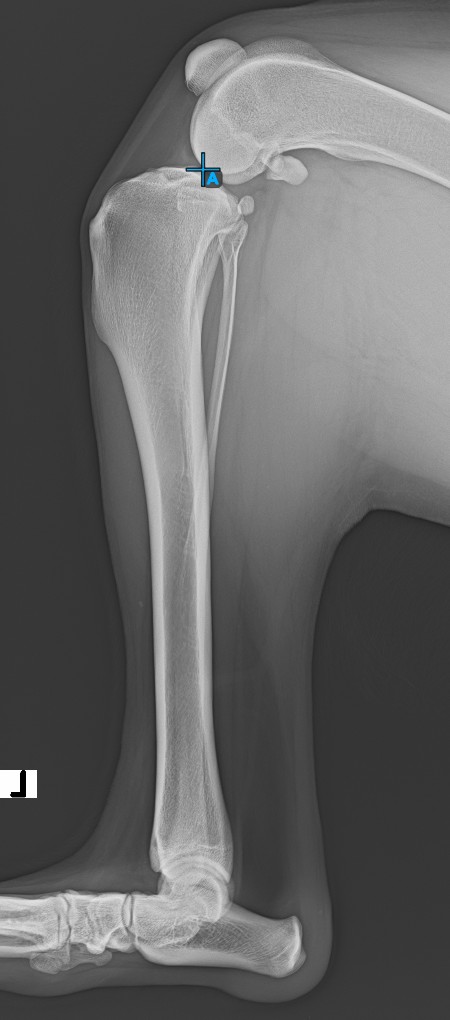

Kezdje el a mérést az Eminentia Intercondylaris megjelölésével, amely a combcsontot és a tibia csontot összekötő ízületnél található.

A lenti kép az Eminentia Intercondylaris pont szokásos elhelyezkedését ábrázolja.